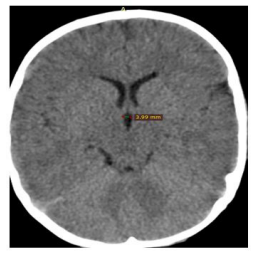

| Figure 2:Axial CT image of the brain showing the maximum height of the third ventricle |

Third ventricle was marked as a mid-line structure between right and left thalami. Width of third ventricle was measured in mm (millimeters) at the level of interventricular foramen (foramen of Monro) and was taken as the maximum distance between the two thalami at this level. The height of the third ventricle could not be measured as its posterior marker the pineal gland was not seen in CT scan sections of all patients. The maximum third ventricular width (Figure 1) and the maximum third ventricular height (Figure 2) were measured in mm. The data were entered into Ipinfo, version 7 and analyzed using the IBM SPSS Statistics, version 20. The means (± standard deviation), ranges, minimum, maximum, and the 95% confidence intervals for the mean (in order to include the true population, mean in 95% of the cases) were all calculated. P- Value less than 0.05 is considered as statistically significant.